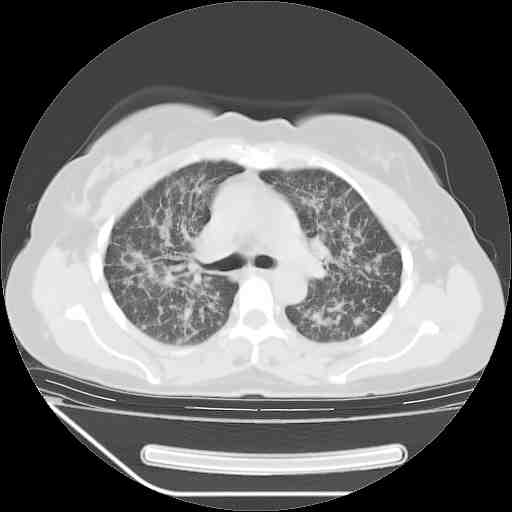

考虑  腺癌肺内转移,治疗较前病灶缩小、减少

支持肺癌并肺内淋巴管炎,  原发灶小了,但转移较前片明显了.

支持右肺下叶周围型肺癌并肺内淋巴管炎,  原发灶小了,但转移较前片明显了.。

标准的细支气管肺泡癌呀!治疗后病情有所控制,也没治愈的迹象!

支持右肺下叶周围型肺癌并肺内淋巴管炎;病灶有所控制。

支持右肺下叶周围型肺癌并肺内淋巴管炎,  原发灶小了,但转移较前片明显了.

应该是比较典型的细支气管炎,4个月的时间不说明问题;有时候疾病是有个相对稳定期的,如果喝10元一斤的茶叶估计也会这样。